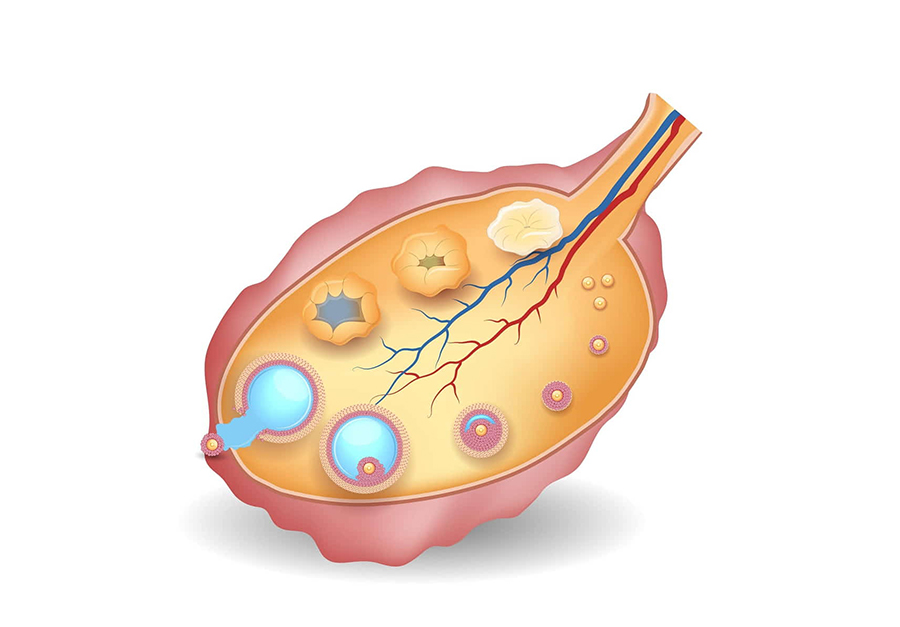

Cấu trúc của nang trứng thay đổi động theo từng giai đoạn phát triển, từ nang nguyên thủy (chỉ có noãn và một lớp tế bào dẹt) đến nang trưởng thành (cấu trúc phức tạp với nhiều lớp tế bào hạt và vỏ). Sự biệt hóa này là cơ sở cho việc sản xuất hormone và chuẩn bị cho sự rụng trứng (Theo Trường Cao đẳng Sản phụ khoa Hoa Kỳ – ACOG).

Quá trình phát triển của nang trứng là một hành trình chọn lọc, bắt đầu từ một nhóm nang nguyên thủy được chiêu mộ, trải qua các giai đoạn sơ cấp, thứ cấp và nang có hốc. Chỉ một nang vượt trội (dominant follicle) đạt đến độ trưởng thành cuối cùng để rụng trứng, trong khi các nang khác thoái hóa (atresia) (Theo Tạp chí Y học New England, 2020).

Ảnh trên: Nang trứng

Quá trình phát triển của nang trứng (folliculogenesis) được chia thành nhiều giai đoạn, tương ứng với các loại nang trứng khác nhau về hình thái và chức năng (Theo Sách giáo khoa Y khoa Merck). Các giai đoạn này bao gồm nang trứng nguyên thủy, nang trứng sơ cấp, nang trứng thứ cấp, và nang trứng trưởng thành (nang Graaf).

Nang trứng nguyên thủy (Primordial Follicle) là gì?

Nang trứng nguyên thủy là giai đoạn “nghỉ”, bao gồm một noãn được bao bọc bởi một lớp tế bào hạt dẹt (Theo Tạp chí Nature Reviews Endocrinology, 2022). Một người phụ nữ được sinh ra với toàn bộ số lượng nang trứng nguyên thủy (khoảng 1-2 triệu) và số lượng này chỉ giảm đi theo thời gian.

Nang trứng sơ cấp (Primary Follicle) là gì?

Nang trứng sơ cấp phát triển từ nang nguyên thủy khi các tế bào hạt dẹt chuyển thành hình khối và bắt đầu phân chia, tạo thành nhiều lớp (Theo Đại học California, San Francisco). Giai đoạn này, noãn bắt đầu tăng kích thước và hình thành màng trong suốt (zona pellucida) bảo vệ.

Nang trứng thứ cấp (Secondary Follicle) là gì?

Nang trứng thứ cấp được đặc trưng bởi sự hình thành nhiều lớp tế bào hạt và sự xuất hiện của hai lớp tế bào vỏ (theca interna và theca externa) (Theo Sách Sinh lý học Ganong). Các tế bào vỏ bắt đầu sản xuất androgen, tiền chất quan trọng để tổng hợp estrogen.

Nang trứng trưởng thành (Mature/Graafian Follicle) là gì?

Nang trứng trưởng thành (còn gọi là nang Graaf) là giai đoạn cuối cùng, đặc trưng bởi một hốc lớn chứa đầy dịch nang (antrum) đẩy noãn và các tế bào hạt ra sát vách (Theo NIH). Nang này có kích thước lớn nhất và là nang duy nhất sẵn sàng cho việc rụng trứng trong chu kỳ.